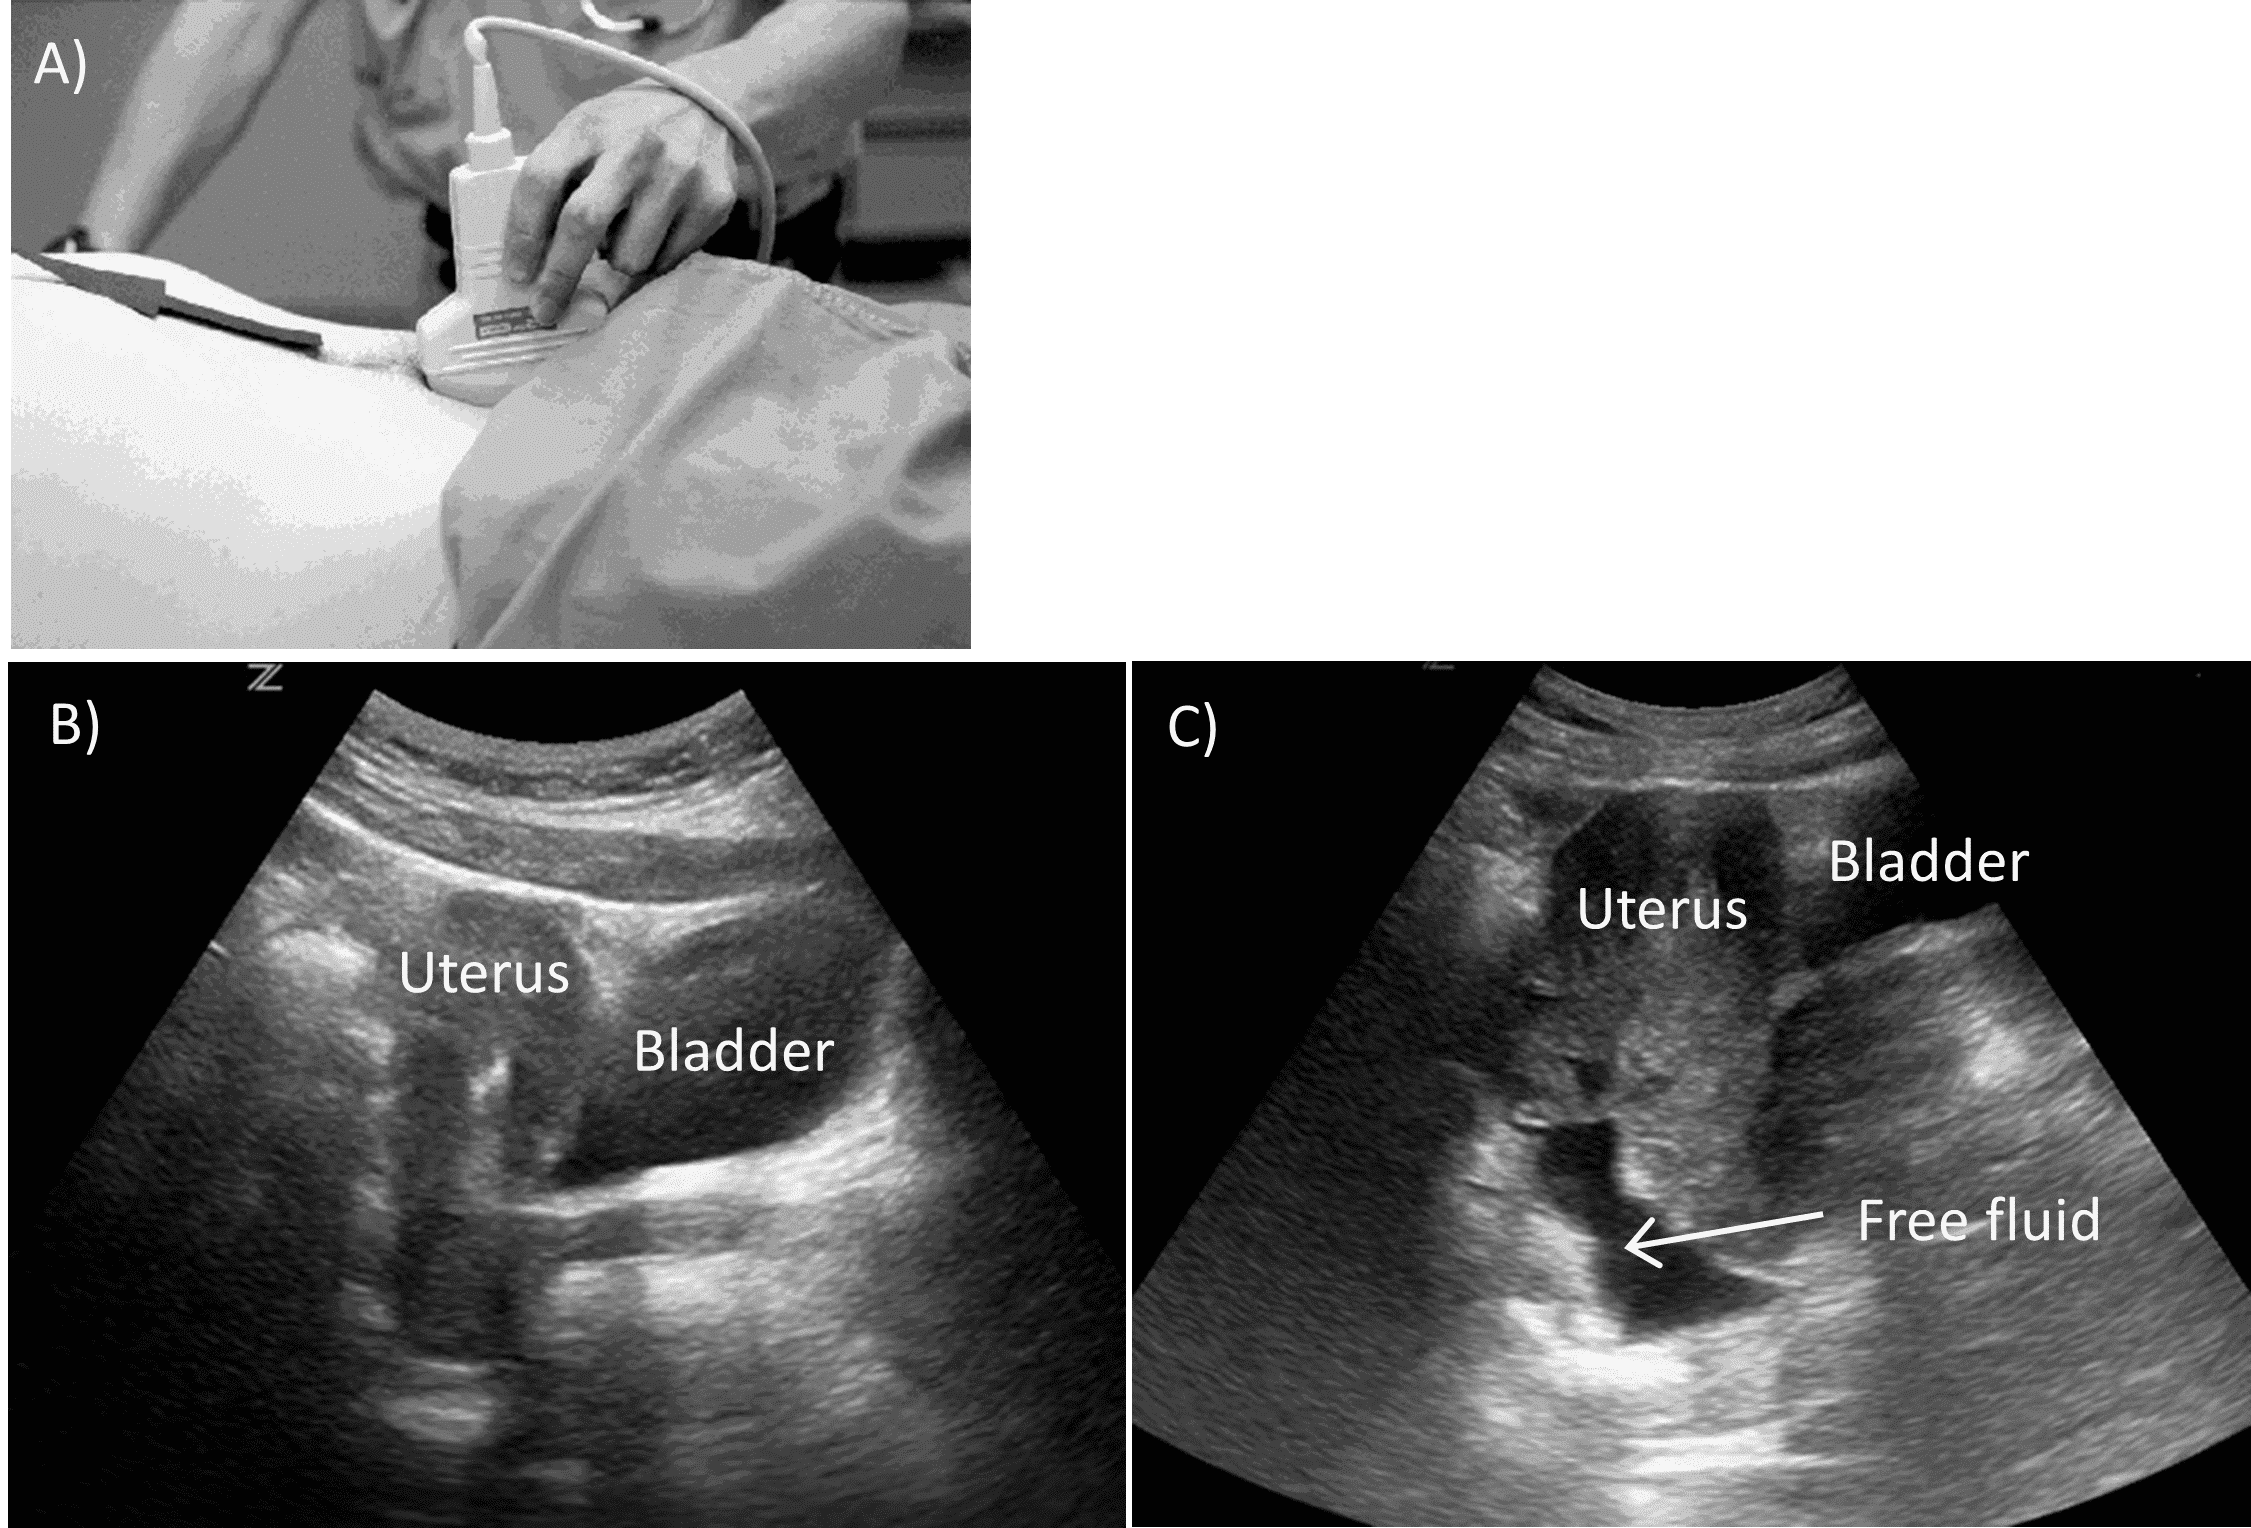

The pelvis is the most dependent area of the abdomen and may be the first place to accumulate fluid. The pelvic view is obtained by placing the probe just superior to the pubic symphysis with the indicator pointed towards the patient’s head. This provides a sagittal view of the bladder. The probe is then moved from side to side to evaluate for fluid behind the bladder (Figure 7).

Sagittal Pelvic View.

A) Probe positioning. B) Normal view. C) Positive view with free fluid.

It is important to visualize the pubic symphysis (which appears as a hyperechoic structure) as the bladder will arise anterior to it. Again, similar to all other views of the FAST exam, adjusting probe position by fanning can assist in obtaining better images and enhance sensitivity. Turning the probe in the transverse orientation, with the indicator pointed to the patient’s right, will provide an axial orientation of the bladder and can help identify fluid on either side, as well as distortion of the bladder itself. Under-distention of the bladder impairs visualization of small volumes of pelvic fluid.

If the patient has a foley catheter in place, the bladder may be filled with 200mL of sterile saline to create a sonographic window. The Pouch of Douglas is the most sensitive area of the pelvic view in women.